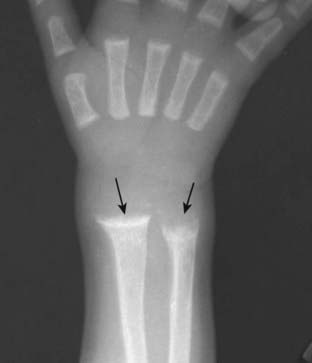

image Osteoporosis predisposes to pathologic fractures in the femoral neck, can lead to compression fractures of the vertebral bodies, and fractures of the distal radius (Colles’ fractures).

image Conventional radiographs are relatively insensitive for detecting osteoporosis. Almost 50% of bone mass must be lost before it is recognizable on conventional radiographs. Findings on conventional radiographs include overall lucency of bone, thinning of the cortex, and decrease in the visible number of trabeculae in the medullary cavity.

image

Figure 21-17 Rickets.

Frontal view of the wrist shows cupping and fraying (solid black arrows) of the metaphyses of the distal radius and ulna, characteristic findings of rickets. Rickets will first affect the bones growing most quickly so it is most common around the knee, distal tibia, and distal radius. It may also be seen at the growing end of the ribs.